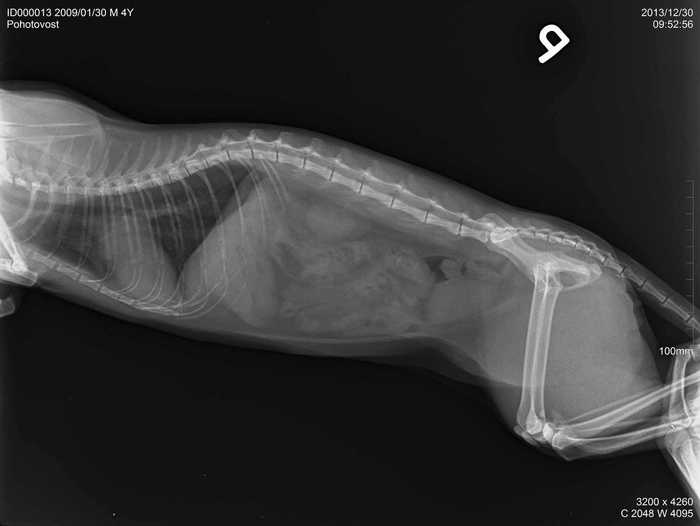

Úvod > Galerie > RTG snímky